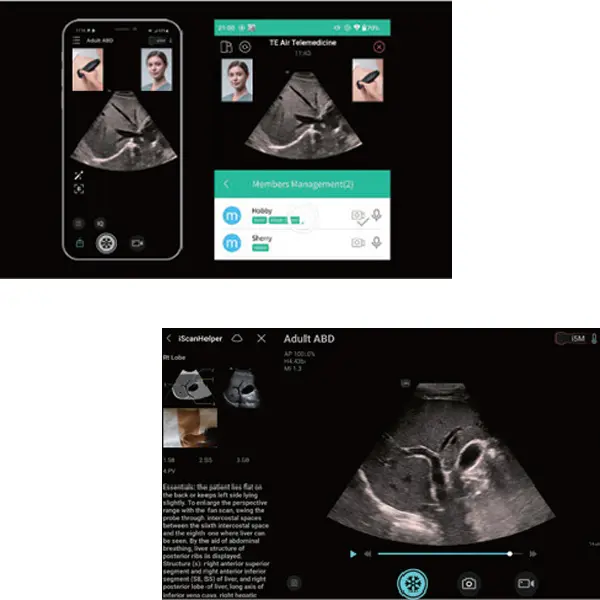

Remote Help

Oблачно базирано решение за колаборация и дистанционна помощ. Remote Help е решението на Mindray за дистанционно съдействие, обучение, контрол на качеството, обсъждане на случаи и други.

Интегрира MiCo+ в приложението, за да споделяте в реално време ултразвукови изображения, синхронизирайки ултразвукови данни, аудио и видео с крайното устройство. Поддръжка за споделяне на оригинални ултразвукови изображения чрез MiCo+.

iScanHelper

Специализиран вграден инструмент за обучение,

който предоставя на потребителите насоки относно

"как" и "какво" при извършване на ултразвукови изследвания. Включва анатомични илюстрации, стандартни ултразвукови изображения, референтни снимки за сканиране и съвети за умело извършване на диагностика. Обхваща приложения за корем, щитовидна жлеза, съдова система, малки части, урология, акушерство и гинекология, FAST протоколи, кардиология и нервна система.